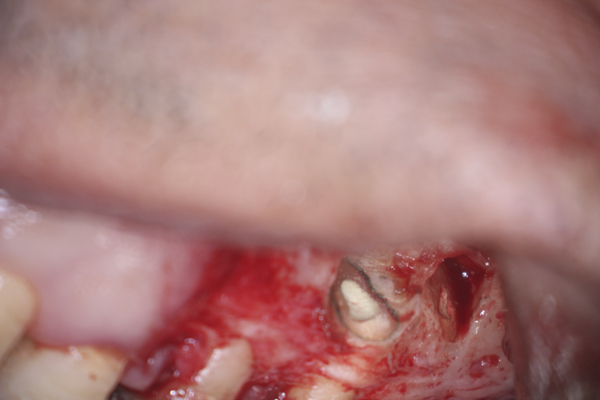

Clinical procedure: In the case of a root-end filling (Figure 15), once the apical 3 mm of the root has been resected (Figure 16) the canal system is then opened and cleaned with surgical ultrasonic tips to create the retro-preparation (Figure 17). After this is completed, the retro-preparation is dried and MTA is then placed and condensed in that space creating the retro-filling (Figure 18 through Figure 20).

Fig 15. Preoperative radiograph.

Figure 15

Fig 16. 3-mm root resection with methylene blue staining.

Figure 16

Fig 17. Retro-preparation with ultrasonic tip.

Figure 17

Fig 18. MTA placed as a retro-filling.

Figure 18

Fig 19. Postoperative radiograph.

Figure 19

Fig 20. 6-month follow-up radiograph.

Figure 20